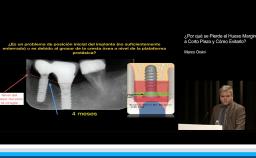

Actualmente la colocación de implantes dentales es un procedimiento clínico que se lleva cabo en la mayoria de las consultas de nuestra geografía. Este aumento pone de manifiesto el gran número de implantes colocados por año en detrimento de la conservación de los dientes de los pacientes. Este crecimiento asociado a la, en ocasiones, poca especialización de los profesionales, hace que también se incremente el porcentaje de complicaciones estéticas y biológicas de los mismos. Hoy en día los pacientes son más exigentes, la estética adquiere un rol decisivo en la percepción del éxito o fracaso de un tratamiento por parte de los mismos. Conocer estos y otros elementos se hace necesario a la hora de establecer un plan de tratamiento definitivo, considerando que la edad y el sexo son factores determinantes en esta percepción. En la presentación se exponen diferentes situaciones clínicas con sus posibles causas y los procedimientos clínicos para resolverlas, mostrando la evolución de los mismo y el resultado final.